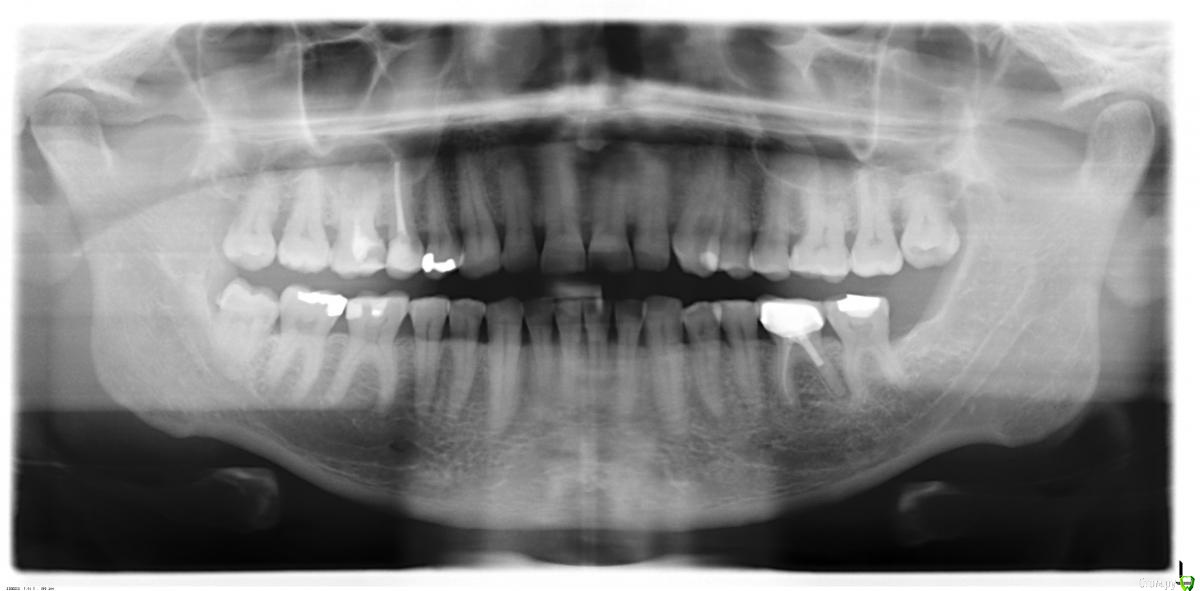

SDC Опубликовано 18 февраля, 2015 Поделиться Опубликовано 18 февраля, 2015 так оно и есть: первый врач - удалять, второй (клиника университетская) - резекция, этого нашел через коллег. Он похоже знает что надо делать, но до сих пор не имел дела с "русской" спецификой.Искать бывшего соотечественника сложно - городишко наш небольшой. Передайте, что если санкции продолжатся, то скоро все "русские зубы" будут такими и держите наготове телефон с открытым инстаграмм - немецкие одонтологи с ума сойдут.А где лечили 15 зуб и 36?На дистальном корне 36 тоже проблемка есть. Вы немецким коллегам подскажите, что небный (палатинальный) канал прямой и пройти его на 1/2 может студент в России.В области верхушек вестибулярных/щечных корней вроде бы нет воспаления в периодонте.Немец из университесткой не может пройти прямой канал, но рекомендует апико небного корня? (это можно сделать только со стороны неба и очень сложно) Ну и в конце концов, не так дорого и в Россию смотаться, особенно, если платят в евро, а все авиакомпании сильно просели в отношении стоимости перелетов. Ссылка на комментарий

DmitrySH Опубликовано 18 февраля, 2015 Поделиться Опубликовано 18 февраля, 2015 Подумав добавлю, что если нет опыта работы с такими зубами - то не надо туда лезть. Процесс давний, не беспокоит. Если не удается осуществить лечение сейчас, оставьте до приезда в Россию. Для нас то такие зубы - обычная рутина. Иначе, скорее всего, кончится удалением Ссылка на комментарий

SDC Опубликовано 18 февраля, 2015 Поделиться Опубликовано 18 февраля, 2015 ...офф топ, что-то в этом браузере цитировать не могу вдруг.. не пойму. Вокруг щечных корней такие небольшие "пузыри". На дистальном чуть больше, примерно 1-1.5 мм вокруг апексаВ общем, КТ надо смотреть - диагностика будет точнее Ссылка на комментарий

red_butler Опубликовано 20 февраля, 2015 Поделиться Опубликовано 20 февраля, 2015 на соседних не отразиться, но такие зубы дают жару в самый не подходящий момент, да и вопрос что уже в верхне-челюстном синусе... как бы потом еще и одонтогенный гайморит не пришлось лечить.как любил говорить руководитель моей интернатуры - "гной в голове - это не хорошо" 1 Ссылка на комментарий